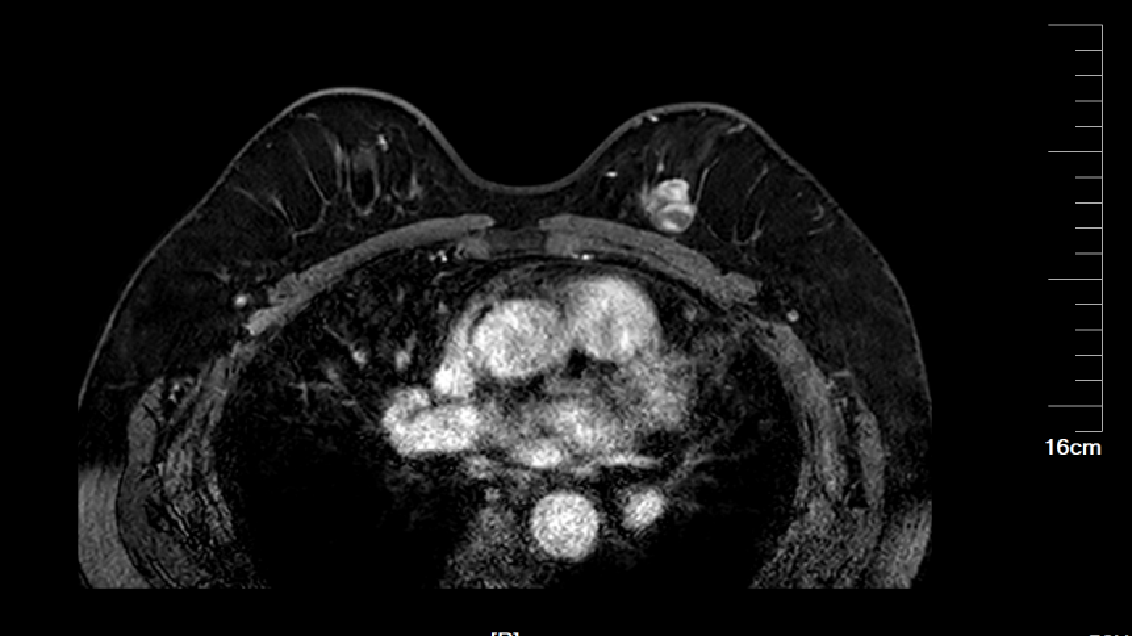

患者李女士(化名)在外院确诊为乳腺癌,这一消息让她及家人陷入巨大的焦虑与无助。经过多方咨询,李女士前来我院乳腺外科张永渠副主任门诊就诊。

乳腺MRI.png

乳腺MRI

经过对患者身体状况的全面评估,并了解到患者对切除乳房的担忧和恐惧后,张永渠副主任为李女士制订了“左乳癌保乳术+肿瘤整形+荧光辅助腋窝前哨淋巴结活检”个体化手术方案。为消除李女士及其家属的顾虑,张主任还通过可视化模型展示了手术原理及预后效果,分享相似病情患者的成功案例。张主任的专业与细致,让李女士重拾信心,最终决定接受手术

术前,张永渠副主任及其团队为李女士开展了术前讨论,排除了保乳手术禁忌症,随后团队制定了保乳手术计划。术中,通过荧光成像技术精准可视化腋窝前哨淋巴结精准,将创伤降到最小,通过肿瘤整形术使得李女士不仅完整地切除了病灶,而且获得了良好的美学外观。术后病理诊断为左乳腺粘液癌 pT1cN0M 0 Ia期,分子分型Luminal A型。经过院内乳腺癌多学科病例讨论,建议患者后续接受放疗、内分泌治疗等综合治疗。在科室医护团队的精细化管理下,李女士恢复状况良好,目前已顺利出院。